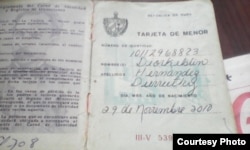

Familiares del niño cubano Diorkeblin Hernández Durruthy, -de 7 años, obeso y postrado en una silla de ruedas por el extraño padecimiento de síndrome de Momo-, denunciaron esta semana que el estatal Centro Internacional de Restauración Neurológica (CIREN) les negó el ingreso y las terapias.

La madre explicó que el niño pesa 64,4 kilogramos y mide 155 centímetros a sus siete años. Además del sobrepeso, padece de asma y trastornos de tiroides.

Este es solo el más reciente de los calvarios sufridos por esta familia residente en Baracoa, Guantánamo. Los padres del niño explicaron que poco después de su nacimiento se dieron cuenta de que algo no andaba bien con el bebé, que crecía de un modo poco común.